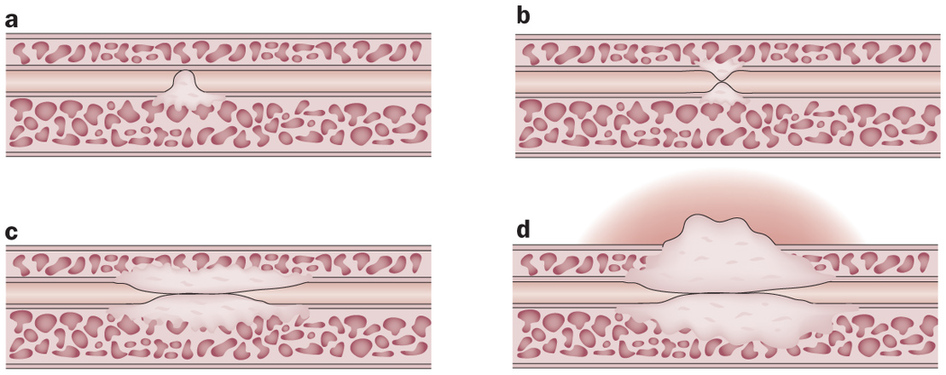

La uretromeatotomía es un procedimiento quirúrgico ambulatorio que se realiza para ampliar el meato uretral y el segmento distal de la uretra cuando existe una estrechez que dificulta la salida normal de la orina 🚻

Es una intervención frecuente en casos de estenosis del meato o estenosis uretral distal.

🏥 ¿Cómo se realiza?

El objetivo es eliminar la obstrucción y restablecer un flujo urinario adecuado.